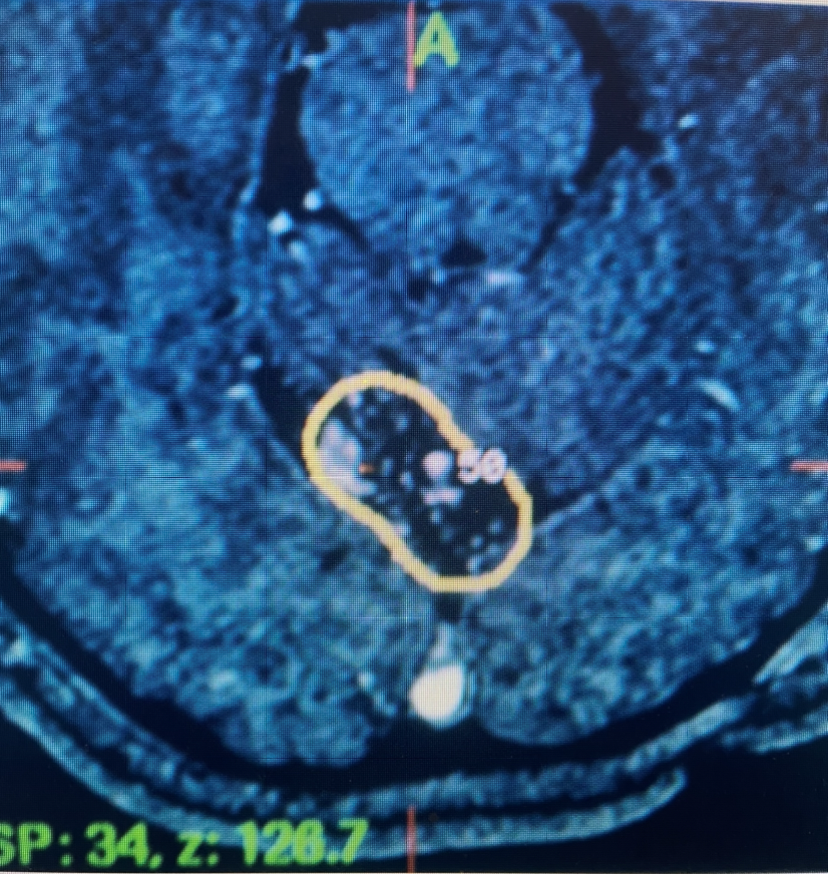

Figure 1. Axial MRI with contrast at the time of gamma knife treatment showing the tightly conformal 50% Isodose line contoured around the AVM of the posterior superior cerebellar vermis.